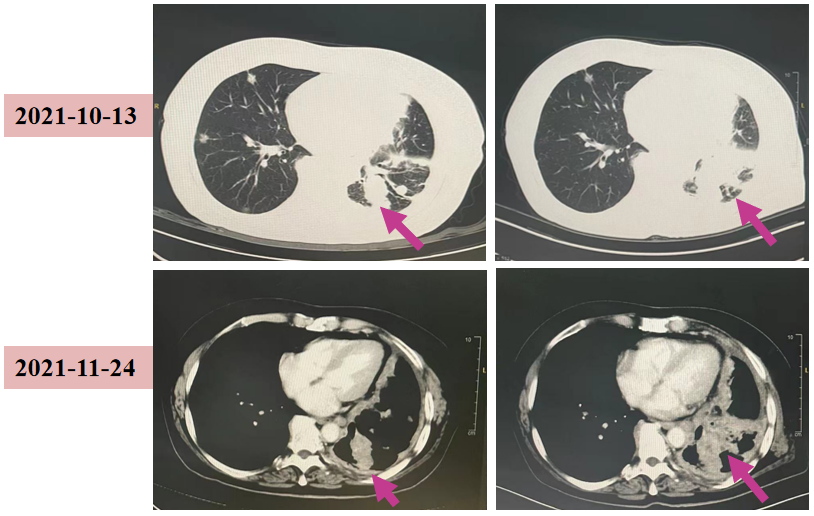

2021-11-24 我院胸部CT:两肺多发结节及团片影,左下肺团片较前增大;评估:PD。